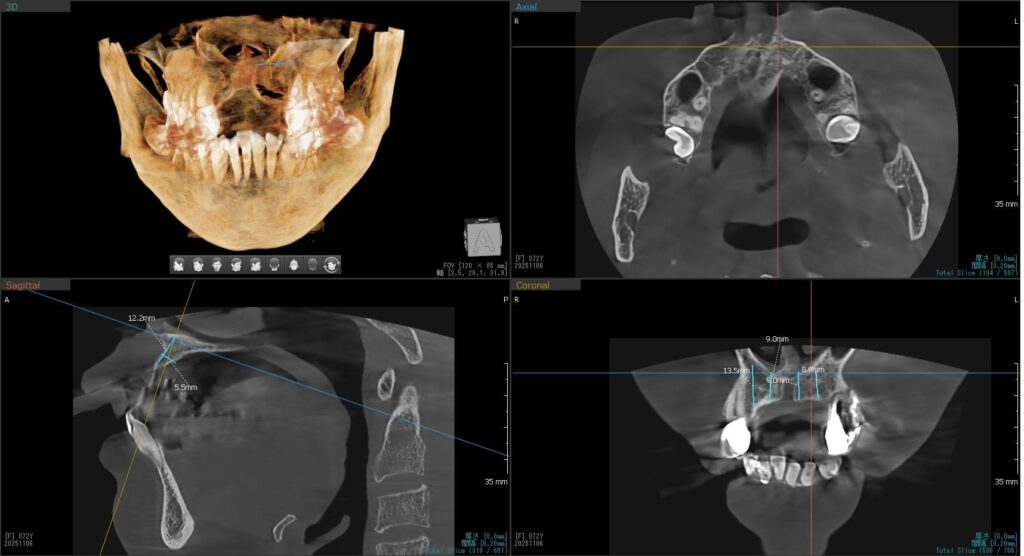

今回の患者様はインプラント植立を希望され、右上1番目・2番目、左上1番目・2番目の合計4本の植立が決まりました。

ドリルの先端を細い物から徐々に大きい物に変えながら、植立するインプラント体のネジの部分を除いた胴の部分の太さに合わせた大きさの穴を開けていきます。

開けた穴に、専用道具を使ってネジを締めるように長さ2センチ程のインプラントを骨に埋め込んでいきます。